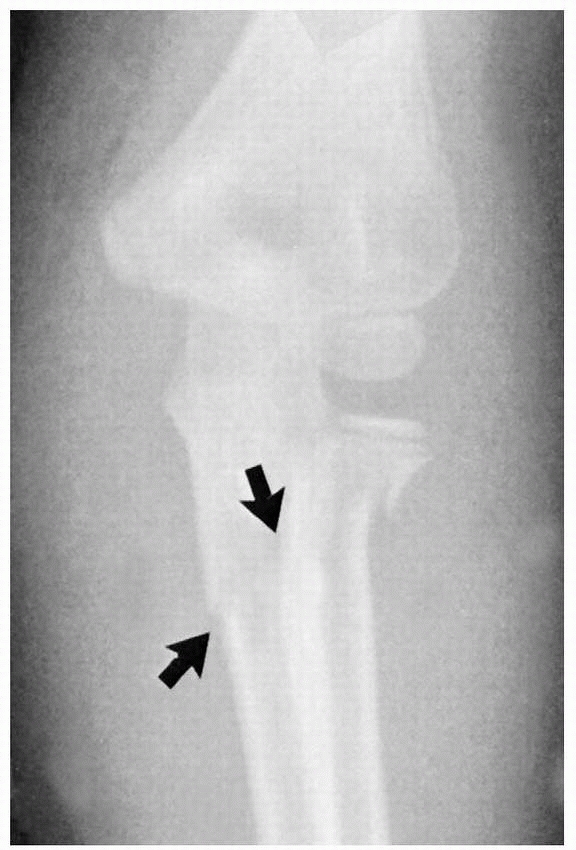

fracture of the radial neck may be difficult in children whose radial

head remains unossified. The only clue may be a little irregularity in

the smoothness of the proximal metaphyseal margin (Fig. 11-3). Rokito et al.93

![]() |

FIGURE 11-3

Preosseous fracture. The only clue to the presence of a fracture of the radial neck with displacement of the radial head was loss of smoothness of the metaphyseal margin (arrow). |